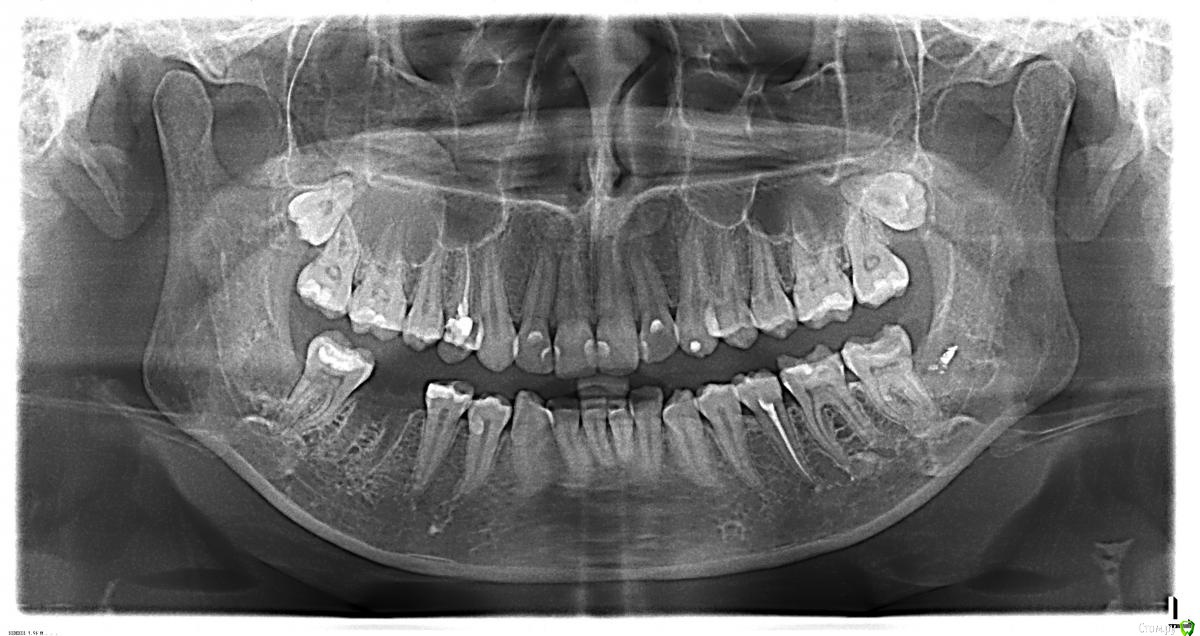

oksanavlasenko87 Опубликовано 21 августа, 2015 Поделиться Опубликовано 21 августа, 2015 (изменено) Добрый деньСитуация такая :4 месяца назад удаляли 8-ки ,лежащие горизонтально под десной.После удаления онемела губа ,нижняя челюсть слева и подбородок,т.е не прошло после анестезии.Проколола уколы мильгамма, стало лучше .но не до конца.5 дней назад лечила зубы на той же стороне,коренные, и на этот раз онемела половина языка! Сегодня снова лечили зуб на левой стороне, доктор сделал анестезию , зная ситуацию , сделал укол в десну рядом с зубом, сказал , что отключит только один зуб, и вот через 20 секунд у меня второй раз онемела половина губы и подбородок ! Прошло 5 часов, никаких признаков жизни ..А я только недавно проколола курс мильгаммыПожалуйста скажите , что может быть причиной? До удаления восьмерок все было в порядке, выкладываю снимки ДО и ПОСЛЕ Изменено 21 августа, 2015 пользователем oksanavlasenko87 Ссылка на комментарий